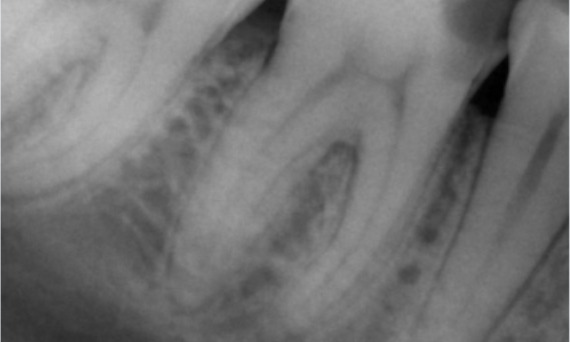

Vorher: Periapikale Radioluzenz primär an der distalen Wurzel und Verlust der Lamina dura an der mesialen Wurzel.

Nachher: In diesem Fall wurde TruNatomy gewählt, um einen kariesfreien Ansatz zu ermöglichen und sich auf den Erhalt des perizervikalen Dentins zu konzentrieren, insbesondere auf der mesialen Seite, wo der Zahn eine minimalere Restauration aufwies.

Vorher: Bei der Untersuchung wurde eine Karies-Läsion am unteren rechten ersten Molaren festgestellt. Bei der röntgenologischen Untersuchung zeigte sich die Nähe der Läsion zum Pulpahorn. Zusammen mit den Hauptbeschwerden wurde die endgültige Diagnose einer chronischen irreversiblen Pulpitis gestellt.

Nachher: Die Zugangskavität wurde so konservativ wie möglich gestaltet. Da es sich um einen jungen Patienten handelte, war TruNatomy das System der Wahl. Wir mussten das Dentin so weit wie möglich erhalten, um die Fähigkeit des Zahns zur Bewältigung der okklusalen Belastung und die Langlebigkeit der endgültigen Restauration zu erhöhen.